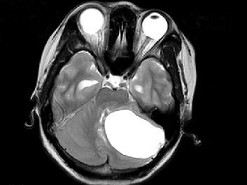

女,27岁,头昏、行走不稳1个月,PE:指鼻试验(+),Romberg氏征(+),根据所提供图像,最可能的诊断()

A.左小脑脓肿

B.左小脑血管母细胞瘤

C.左小脑星形细胞瘤

D.左小脑胶质细胞瘤

E.左小脑转移瘤

女,27岁,头昏、行走不稳1个月,PE:指鼻试验(+),Romberg氏征(+)

[单选题]女,27岁,头昏、行走不稳1个月,PE:指鼻试验(+),Romberg氏征(+),根据所提供图像,最可能的诊断()A . 左小脑脓肿B . 左小脑血管母细胞瘤C . 左小脑星形细胞瘤D . 左小脑胶质细胞瘤E . 左小脑转移瘤